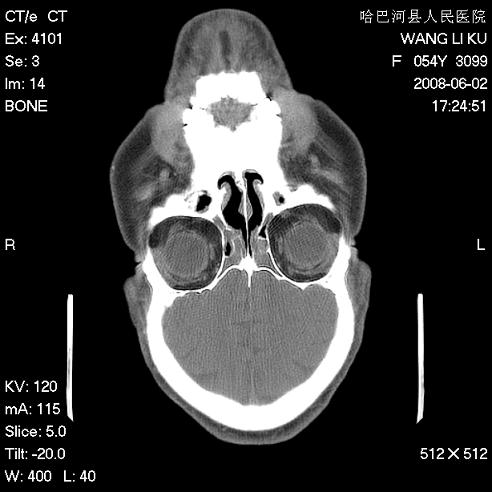

标题: CT13803:反复性鼻塞、流涕一年余 [打印本页]

标题: CT13803:反复性鼻塞、流涕一年余

副鼻窦炎,右上额窦积脓。左眼肌锥内见致密影,视神經受压

1.全组副鼻窦炎2.双侧上颌窦积液

全组副鼻窦炎 肌锥内高密度灶。建议进一步检察检查

1、全组副鼻窦炎。

2、左眼眶肌锥内病变,小血管瘤?建议增强。

1)全副鼻窦炎(左侧上颌窦黏膜下囊肿或息肉)。2)左眼眶肌锥内不规则小结节状软组织密度影;考虑为小血管瘤可能。建议行ct增强扫描检查。

全组副鼻窦炎,左侧肌锥内不规则形软组织肿块影,与眼外肌密度相当,左侧视神经受压,肿块与视神经及眼外肌分界清晰,眼外肌无增粗,眶壁无破坏,球后脂肪间隙不模糊,考虑良性改变,小血管瘤或神经源性肿瘤可能,建议增强扫描。

谢谢,增强扫描做了,眶内病灶与海绵窦同步明显强化,血管瘤